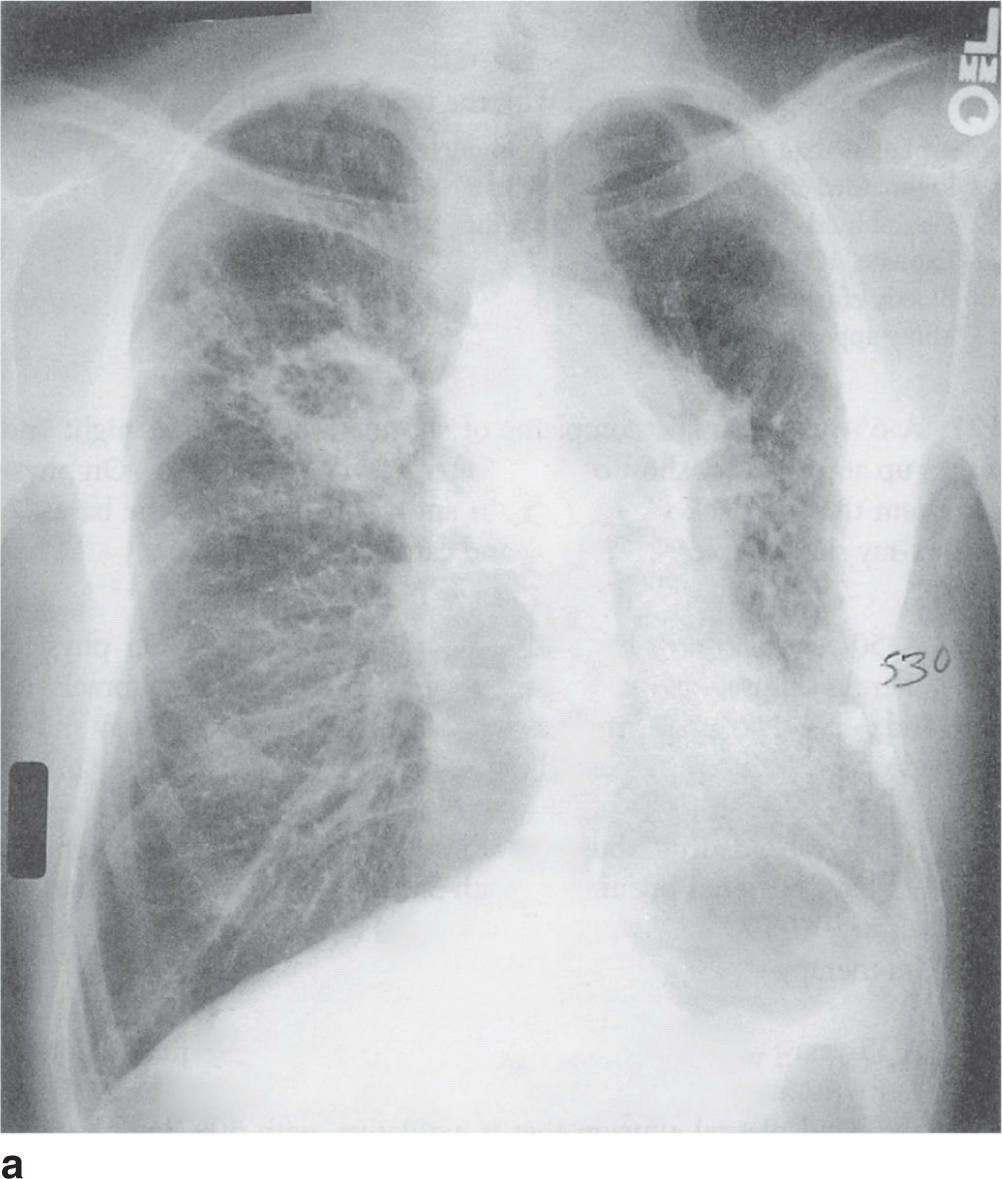

- Khởi phát cấp tính với sốt, ho đàm và ớn lạnh ở bệnh nhân đang nằm viện hậu phẫu gợi ý viêm phổi bệnh viện (HAP). Hình ảnh cầu khuẩn gram dương thành từng đám trên nhuộm Gram gợi ý tụ cầu vàng, là tác nhân thường gặp trong viêm phổi bệnh viện, đặc biệt trên bệnh nhân phẫu thuật hoặc đặt nội khí quản.

- X-quang hình A cho thấy tổn thương khu trú vùng giữa phổi phải, có hình ảnh hoại tử tạo khoang, phù hợp với viêm phổi tụ cầu – có thể diễn tiến thành áp xe phổi nếu khoang lớn hơn 2 cm.